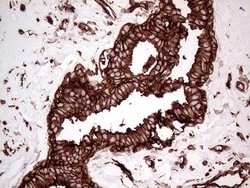

| Immunohistochemistry (Paraffin), Western Blot | |